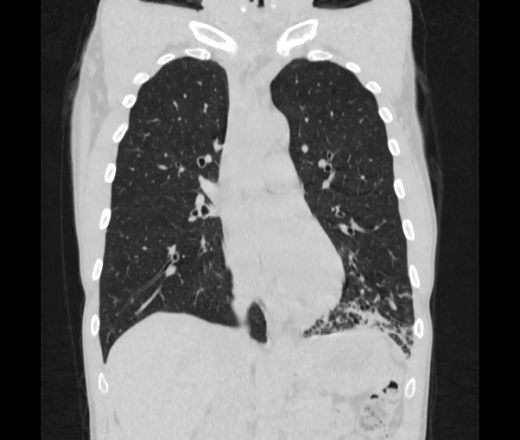

Мужчина пенсионного возраста. Цель назначения КТ ислючение зла в левом легком. Вижу тракционные бронхоэктазы с рубцовой эмфиземой по периферии, скорее всего БЭБ в стадии обострения. Дивертикулы трахеи. Выложил из за того что есть доля сомнения в отношении исключения зно3, немного смущают линии похожие на Керли.